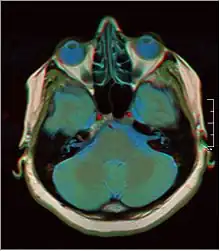

![]() Cross-sectional T1-weighted MRI of a healthy human brain acquired with an ultra high-field MR of 7 Tesla field strength | |

A number of different imaging modalities or sequences can be used with imaging the nervous system:

- T1-weighted (T1W) images: Cerebrospinal fluid is dark. T1-weighted images are useful for visualizing normal anatomy.

- T2-weighted (T2W) images: CSF is light, but fat (and thus white matter) is darker than with T1. T2-weighted images are useful for visualizing pathology.[26]

- Diffusion-weighted images (DWI): DWI uses the diffusion of water molecules to generate contrast in MR images.

- Proton density (PD) images: CSF has a relatively high level of protons, making CSF appear bright. Gray matter is brighter than white matter.[27]

- Fluid attenuation inversion recovery (FLAIR): useful for evaluation of white matter plaques near the ventricles.[28] It is useful in identifying demyelination.[29]